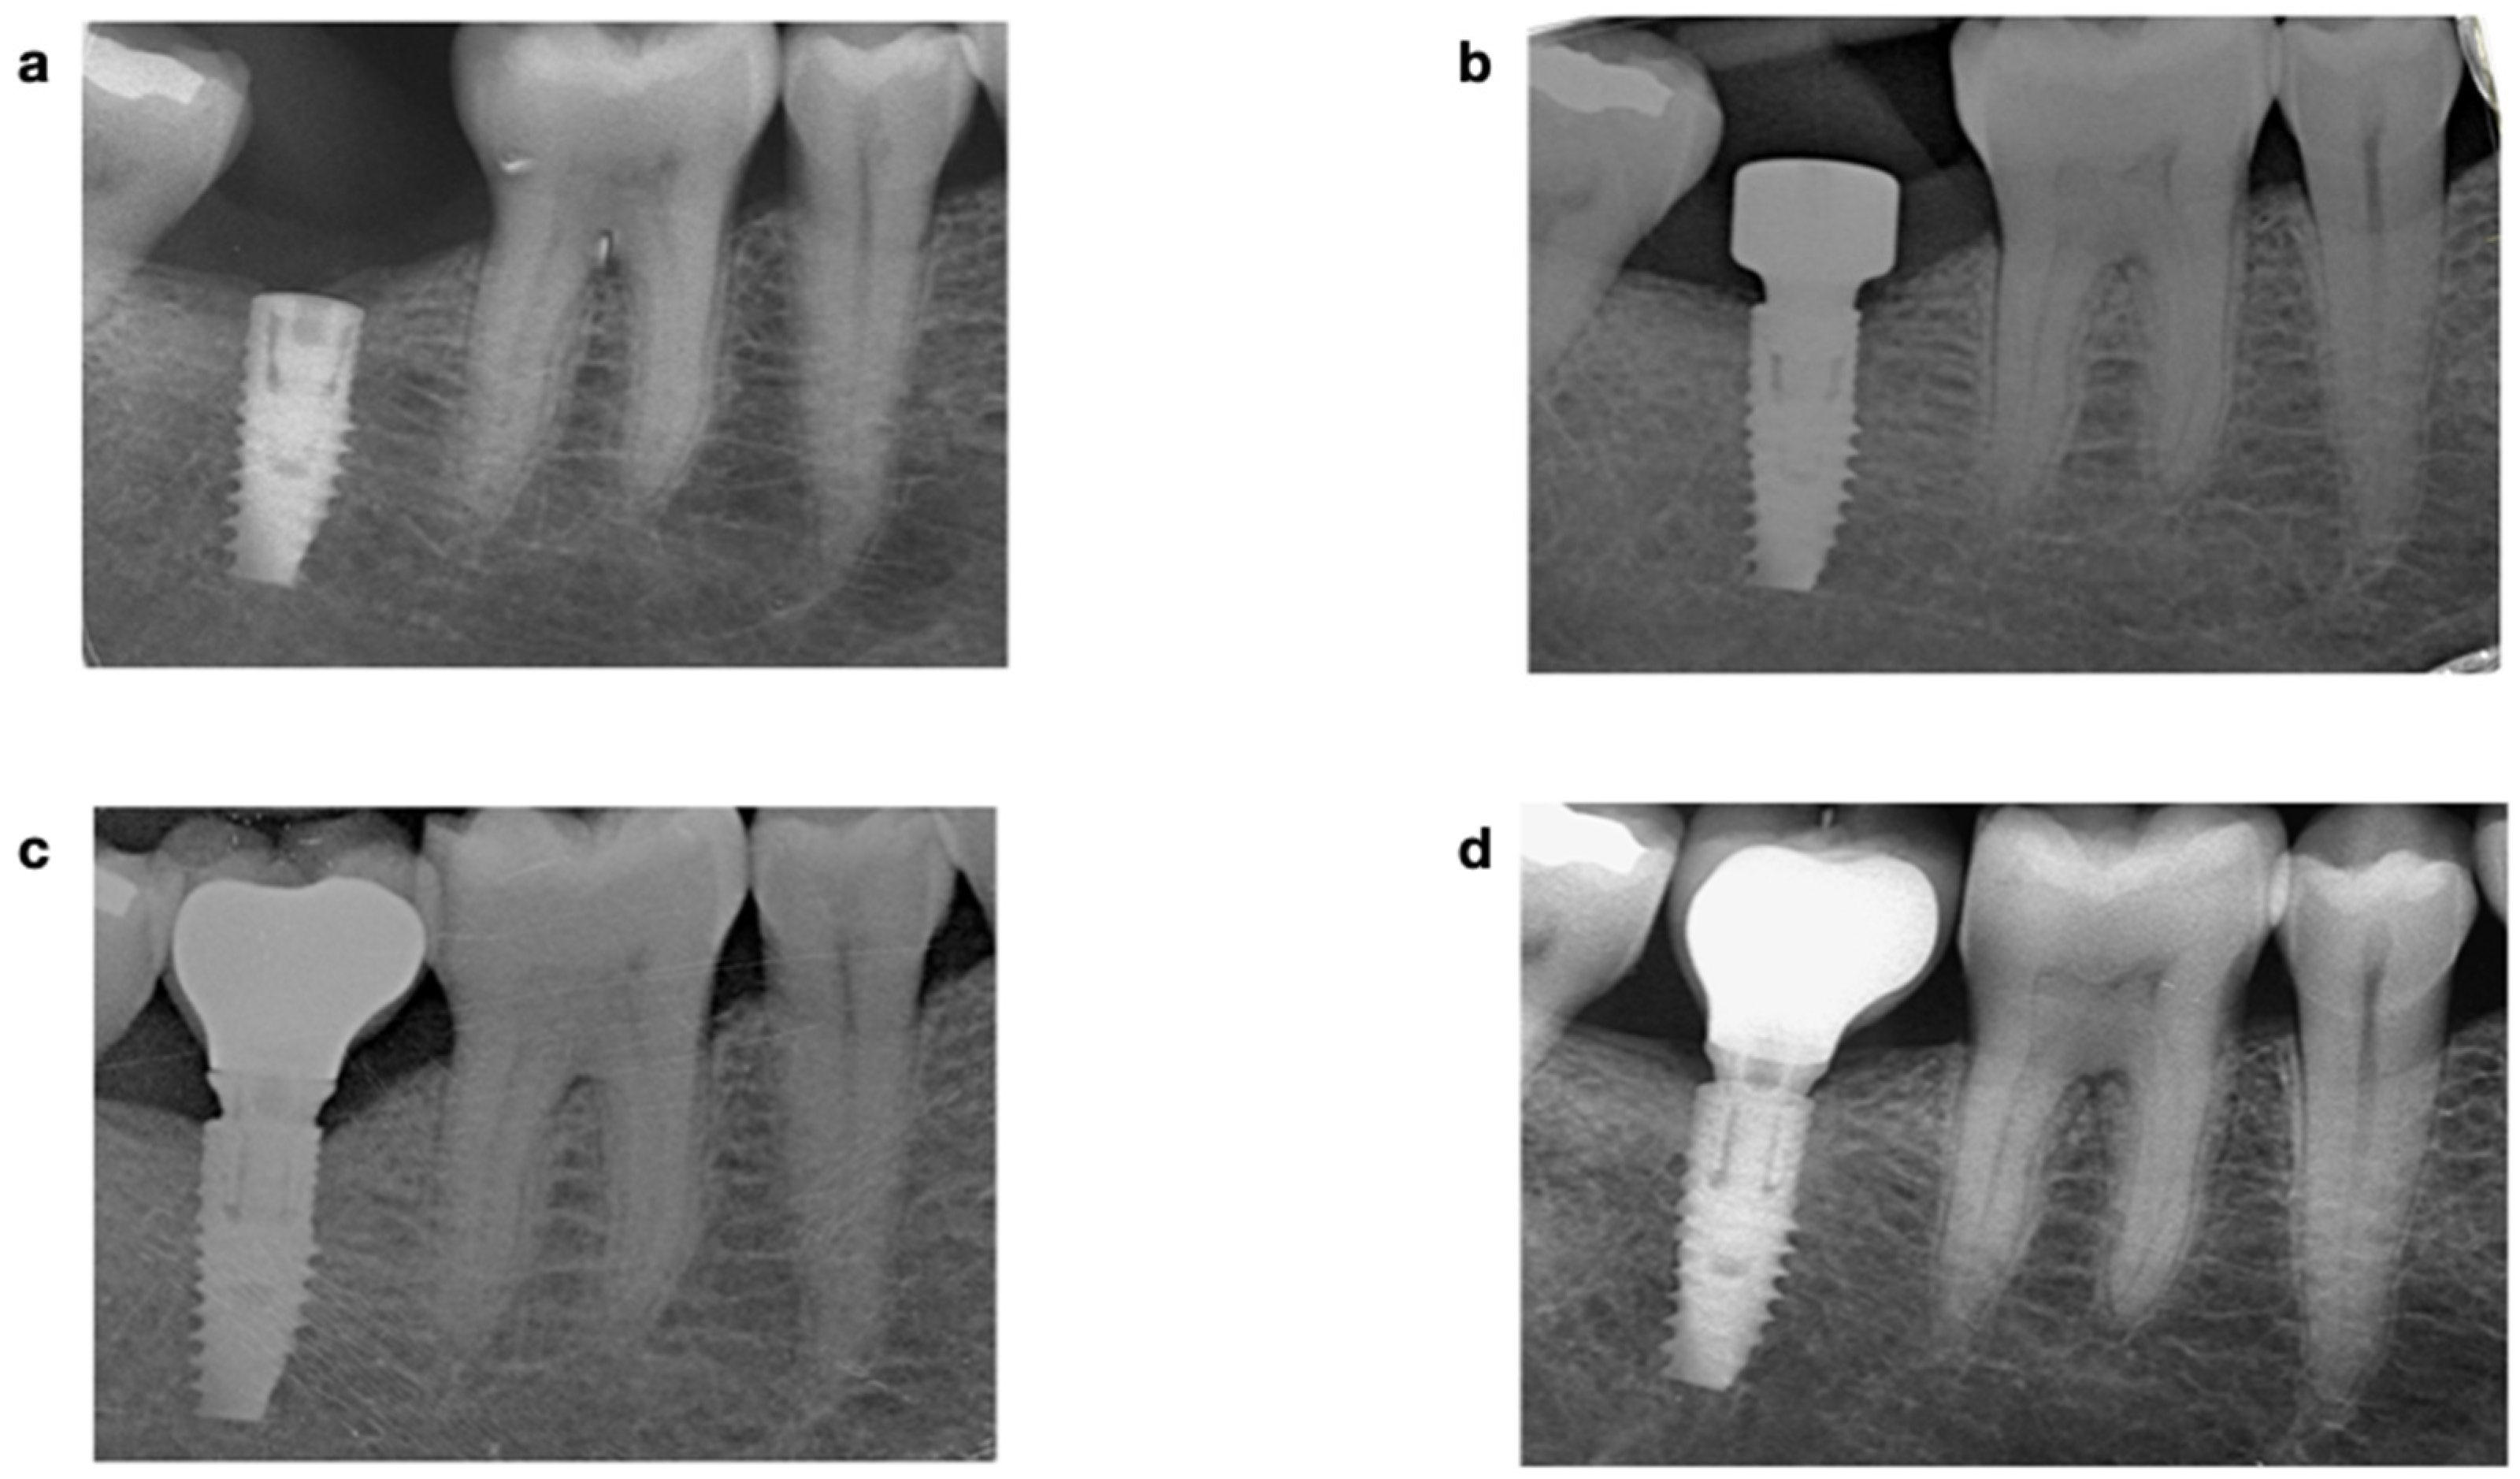

2.4.1. Radiographic Assessment